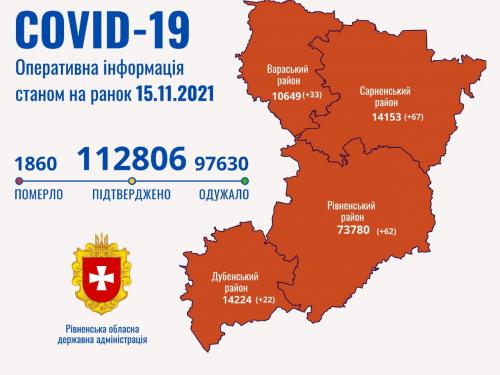

Пів тисячі - у важкому стані, 9 жителів Рівненщини померли за добу від коронавірусу